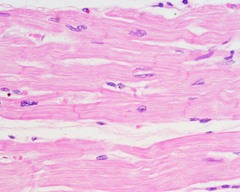

skeletal muscle

Front

A muscle that is attached to the bones of the skeleton and provides the force that moves the bones.